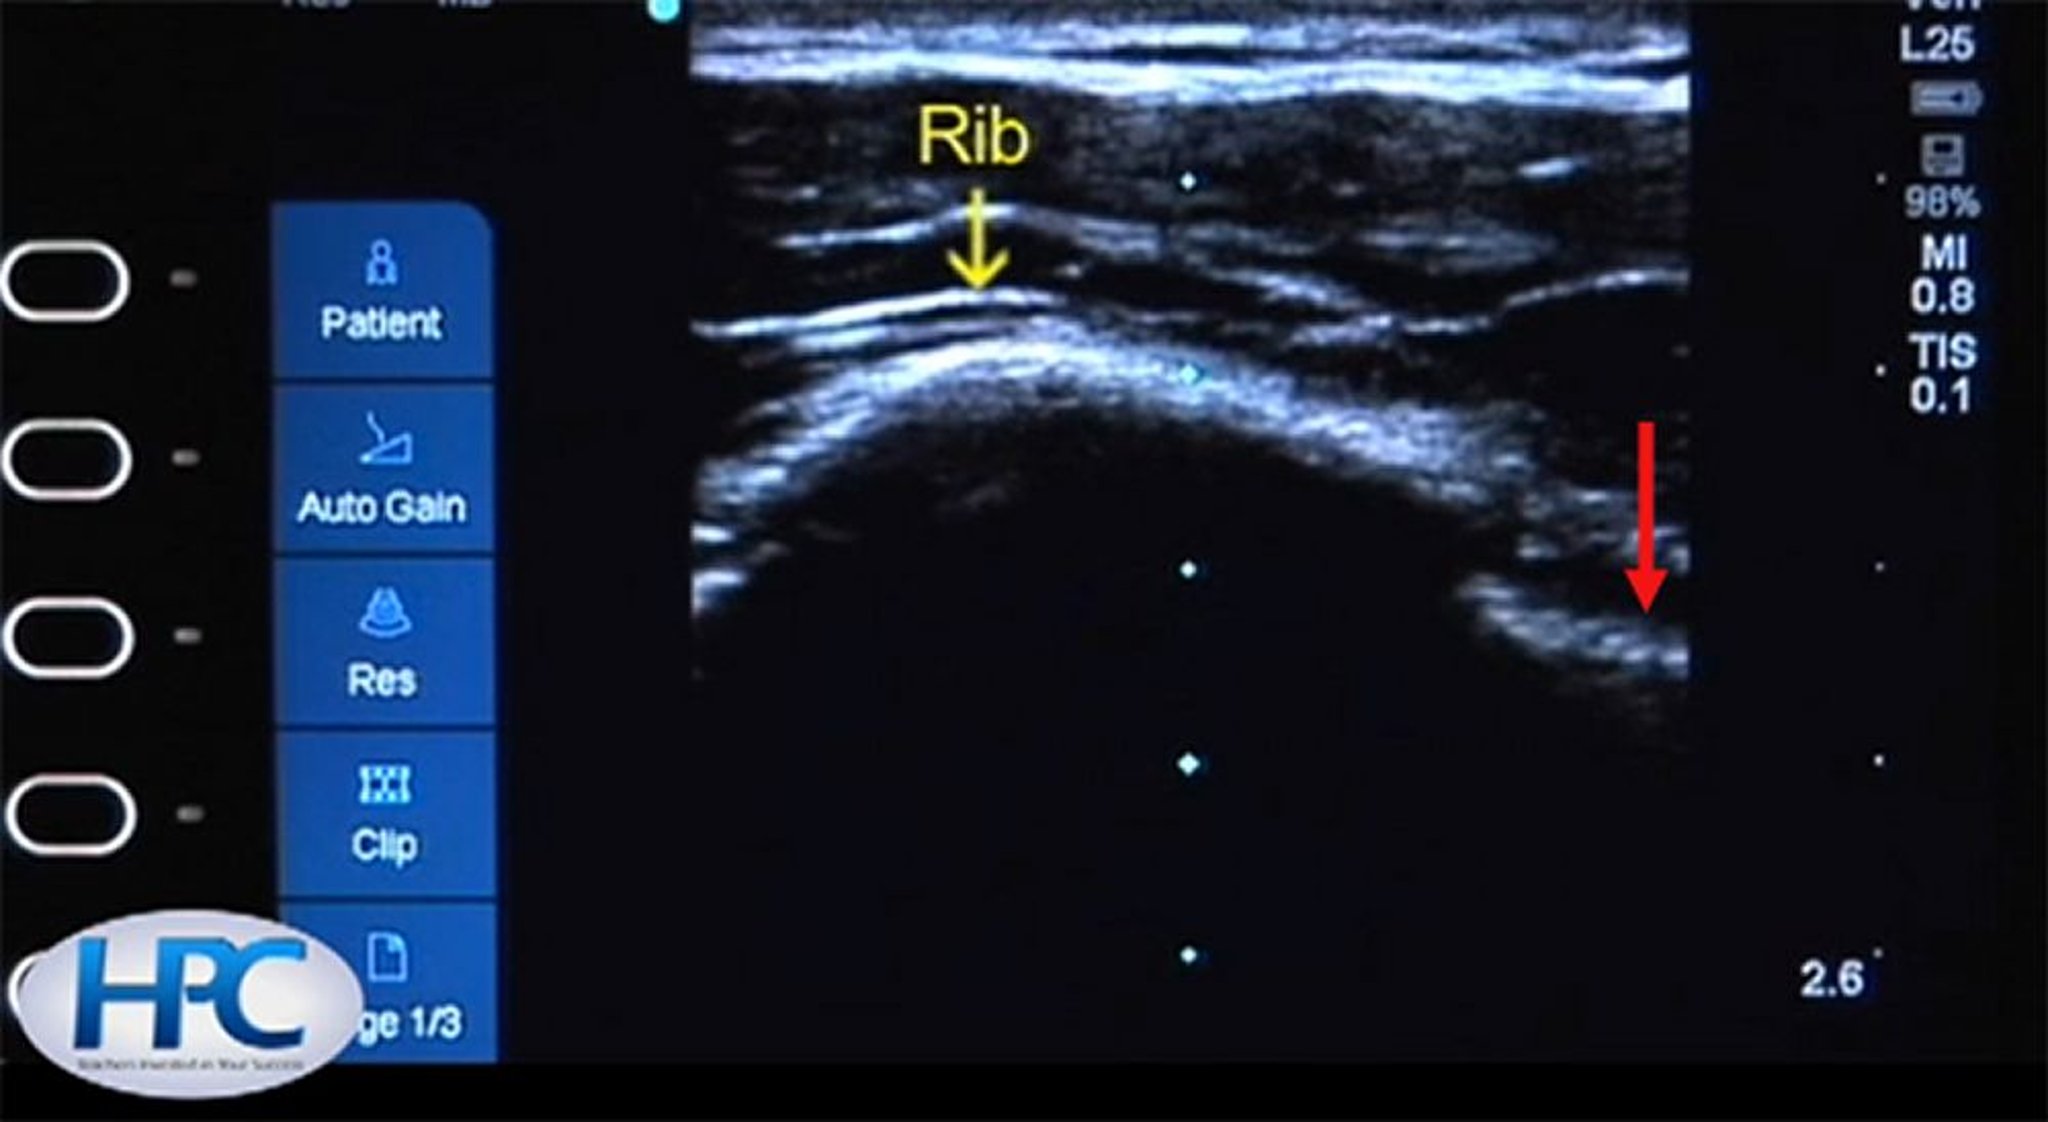

Изображение ребер и линии плевры при ультразвуковом исследовании

Ребро (желтая стрелка) выглядит как гиперэхогенная (белая) структура с затенением ниже ребра. Плевральная линия (красная стрелка) видна в межреберном пространстве.